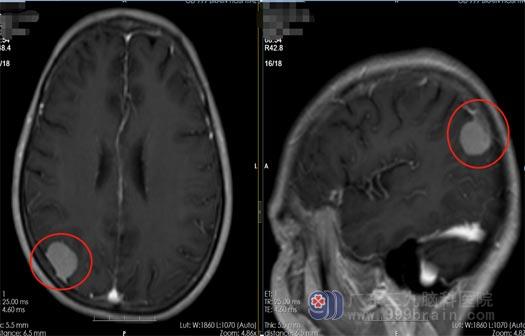

祁阿姨今年65岁,1个月前开始出现双眼视力下降,当时她并不在意,以为是年纪大了眼睛老花了。可是慢慢的她发现看东西的范围也开始逐渐变窄,且左眼伴有流泪感,伴有间断头痛,祁阿姨以为是自己的眼睛出了问题,就去眼科医院检查,可眼科医生看了后却建议她去检查一下颅内的情况,满怀疑惑祁阿姨还是听从了医生的建议做了个头颅MR检查。不查不知道,一查吓一跳:右侧枕部占位性病变、考虑肿瘤性病变。

家人找到了广东三九脑科医院鲁明副院长。完善相关检查后,鲁明及神经外五科主任王国良带领治疗团队进行仔细的病历讨论,入院第三天即在全麻下行右侧枕部脑膜瘤切除术,术中镜下全切肿瘤,血管保护完好,手术顺利结束。